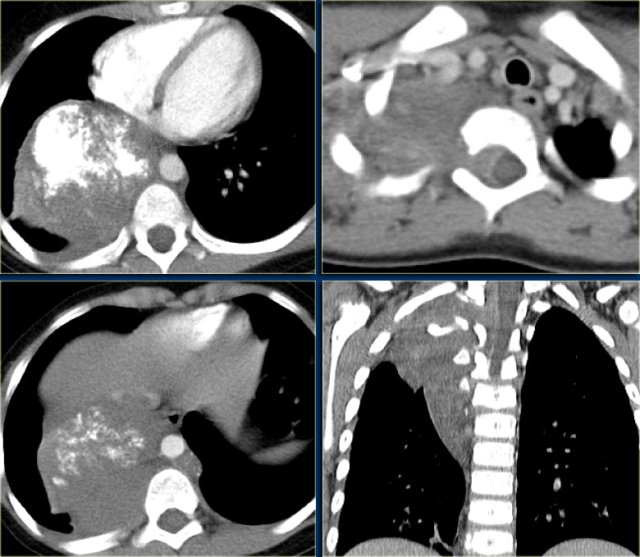

Hodgkin lymphoma Hodgkin lymphoma

The chest film shows the typical features of Hodgkin lymphoma, e.g., an anterior mediastinal mass.

The CT-images of the same patient show a large soft tissue mass in the anterior mediastinum, which arises in the thymus.

There is associated paratracheal adenopathy (arrow).

Two more cases of Hodgkin lymphoma.

Again these cases show an anterior mediastinal mass and paratracheal adenopathy.